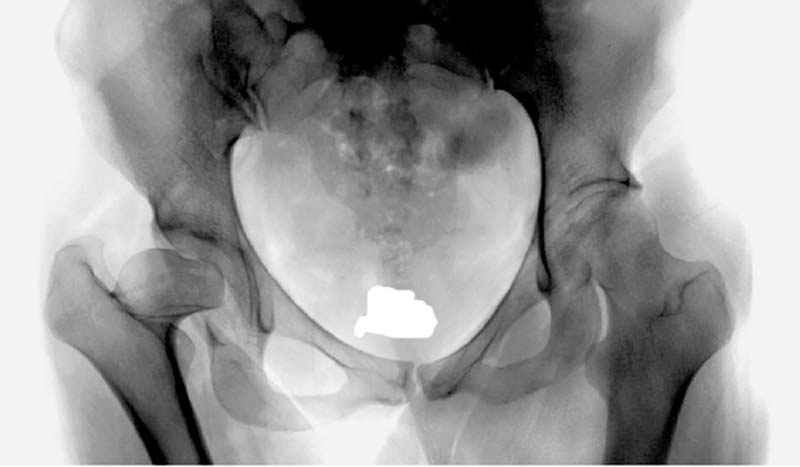

предоперационные снимки #8

предоперационные снимки #9

предоперационные снимки #10

№ 8-10 предоперационные снимки